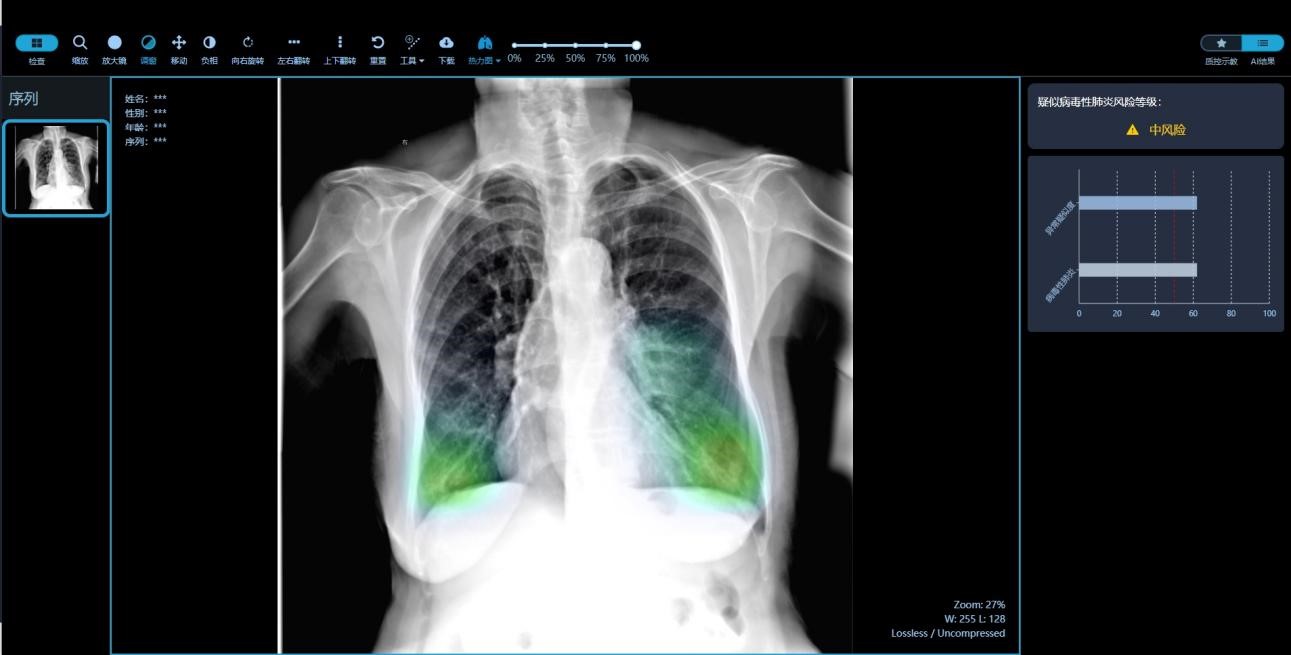

作为江西省2020“专、精、特、新”入选企业,本着“专业化”、“精细化”、“特色化”、“新颖化” 的基本原则,2021年度九峰医疗加大研发资金投入,众多高新技术产品相继上市。其中“5G+AI基层呼吸道传染病监测预警系统”成为拳头产品,该系统通过接入DR设备的终端(九峰牛盒)可自动获取影像数据,运用AI技术能达到秒级识别并监测出疑似病毒性肺炎病例。系统内置的六大预警模型,从大数据的时空规律入手,对传染病疫情进行监测预警,从而实现预警关口前移。该系统为我国传统防控体系下针对农村监测相对薄弱的问题做了有益补充,符合国家提出的智慧化预警多点触发机制。

(“5G+AI基层呼吸道传染病监测预警系统”应用界面图)

(“5G+AI基层呼吸道传染病监测预警系统”胸片界面图)